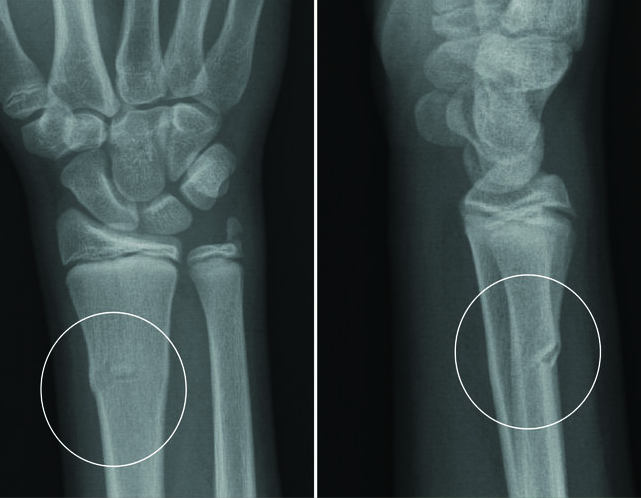

Hva er dette?

Bucklefraktur( torusfraktur). Metafysene hos barn består av mykt ben og tynnere korteks som kan gi etter under kompresjon og forårsake den typiske torusfrakturen. Beskrives som en bulk i en ellers intakt korteks. Stabilt og behandling er generelt smertelindring i noen uker.